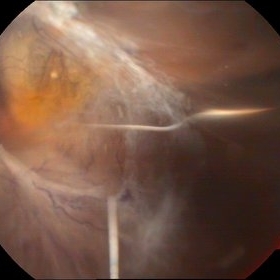

Inverse hypopyon-Emulcified silicon Oil

Apr 24 2015 by Mehul A Shah

Patient had history of vitrectomy with silicon oil injection before 6 years.

Photographer: Mehul Shah

Imaging device: Zeiss FF450plus

Condition/keywords: Inverse hypopyon, silicone oil